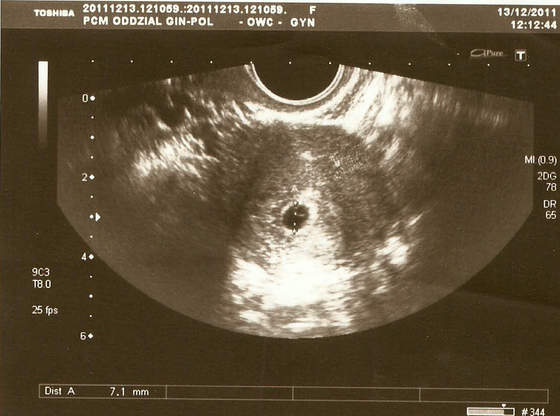

czy mi się wydaje czy na tym pierwszym zdjęciu z 11 w lewym rogu to stópki?

Tak jest, to stópki

Zupełnie mnie to ujęcie rozczula...!Błonka a dlaczego za okrągłe? Mój mały też ma taki zgrabny, okrąglutki pęcherzyk żółtkowy na podorędziu:-)